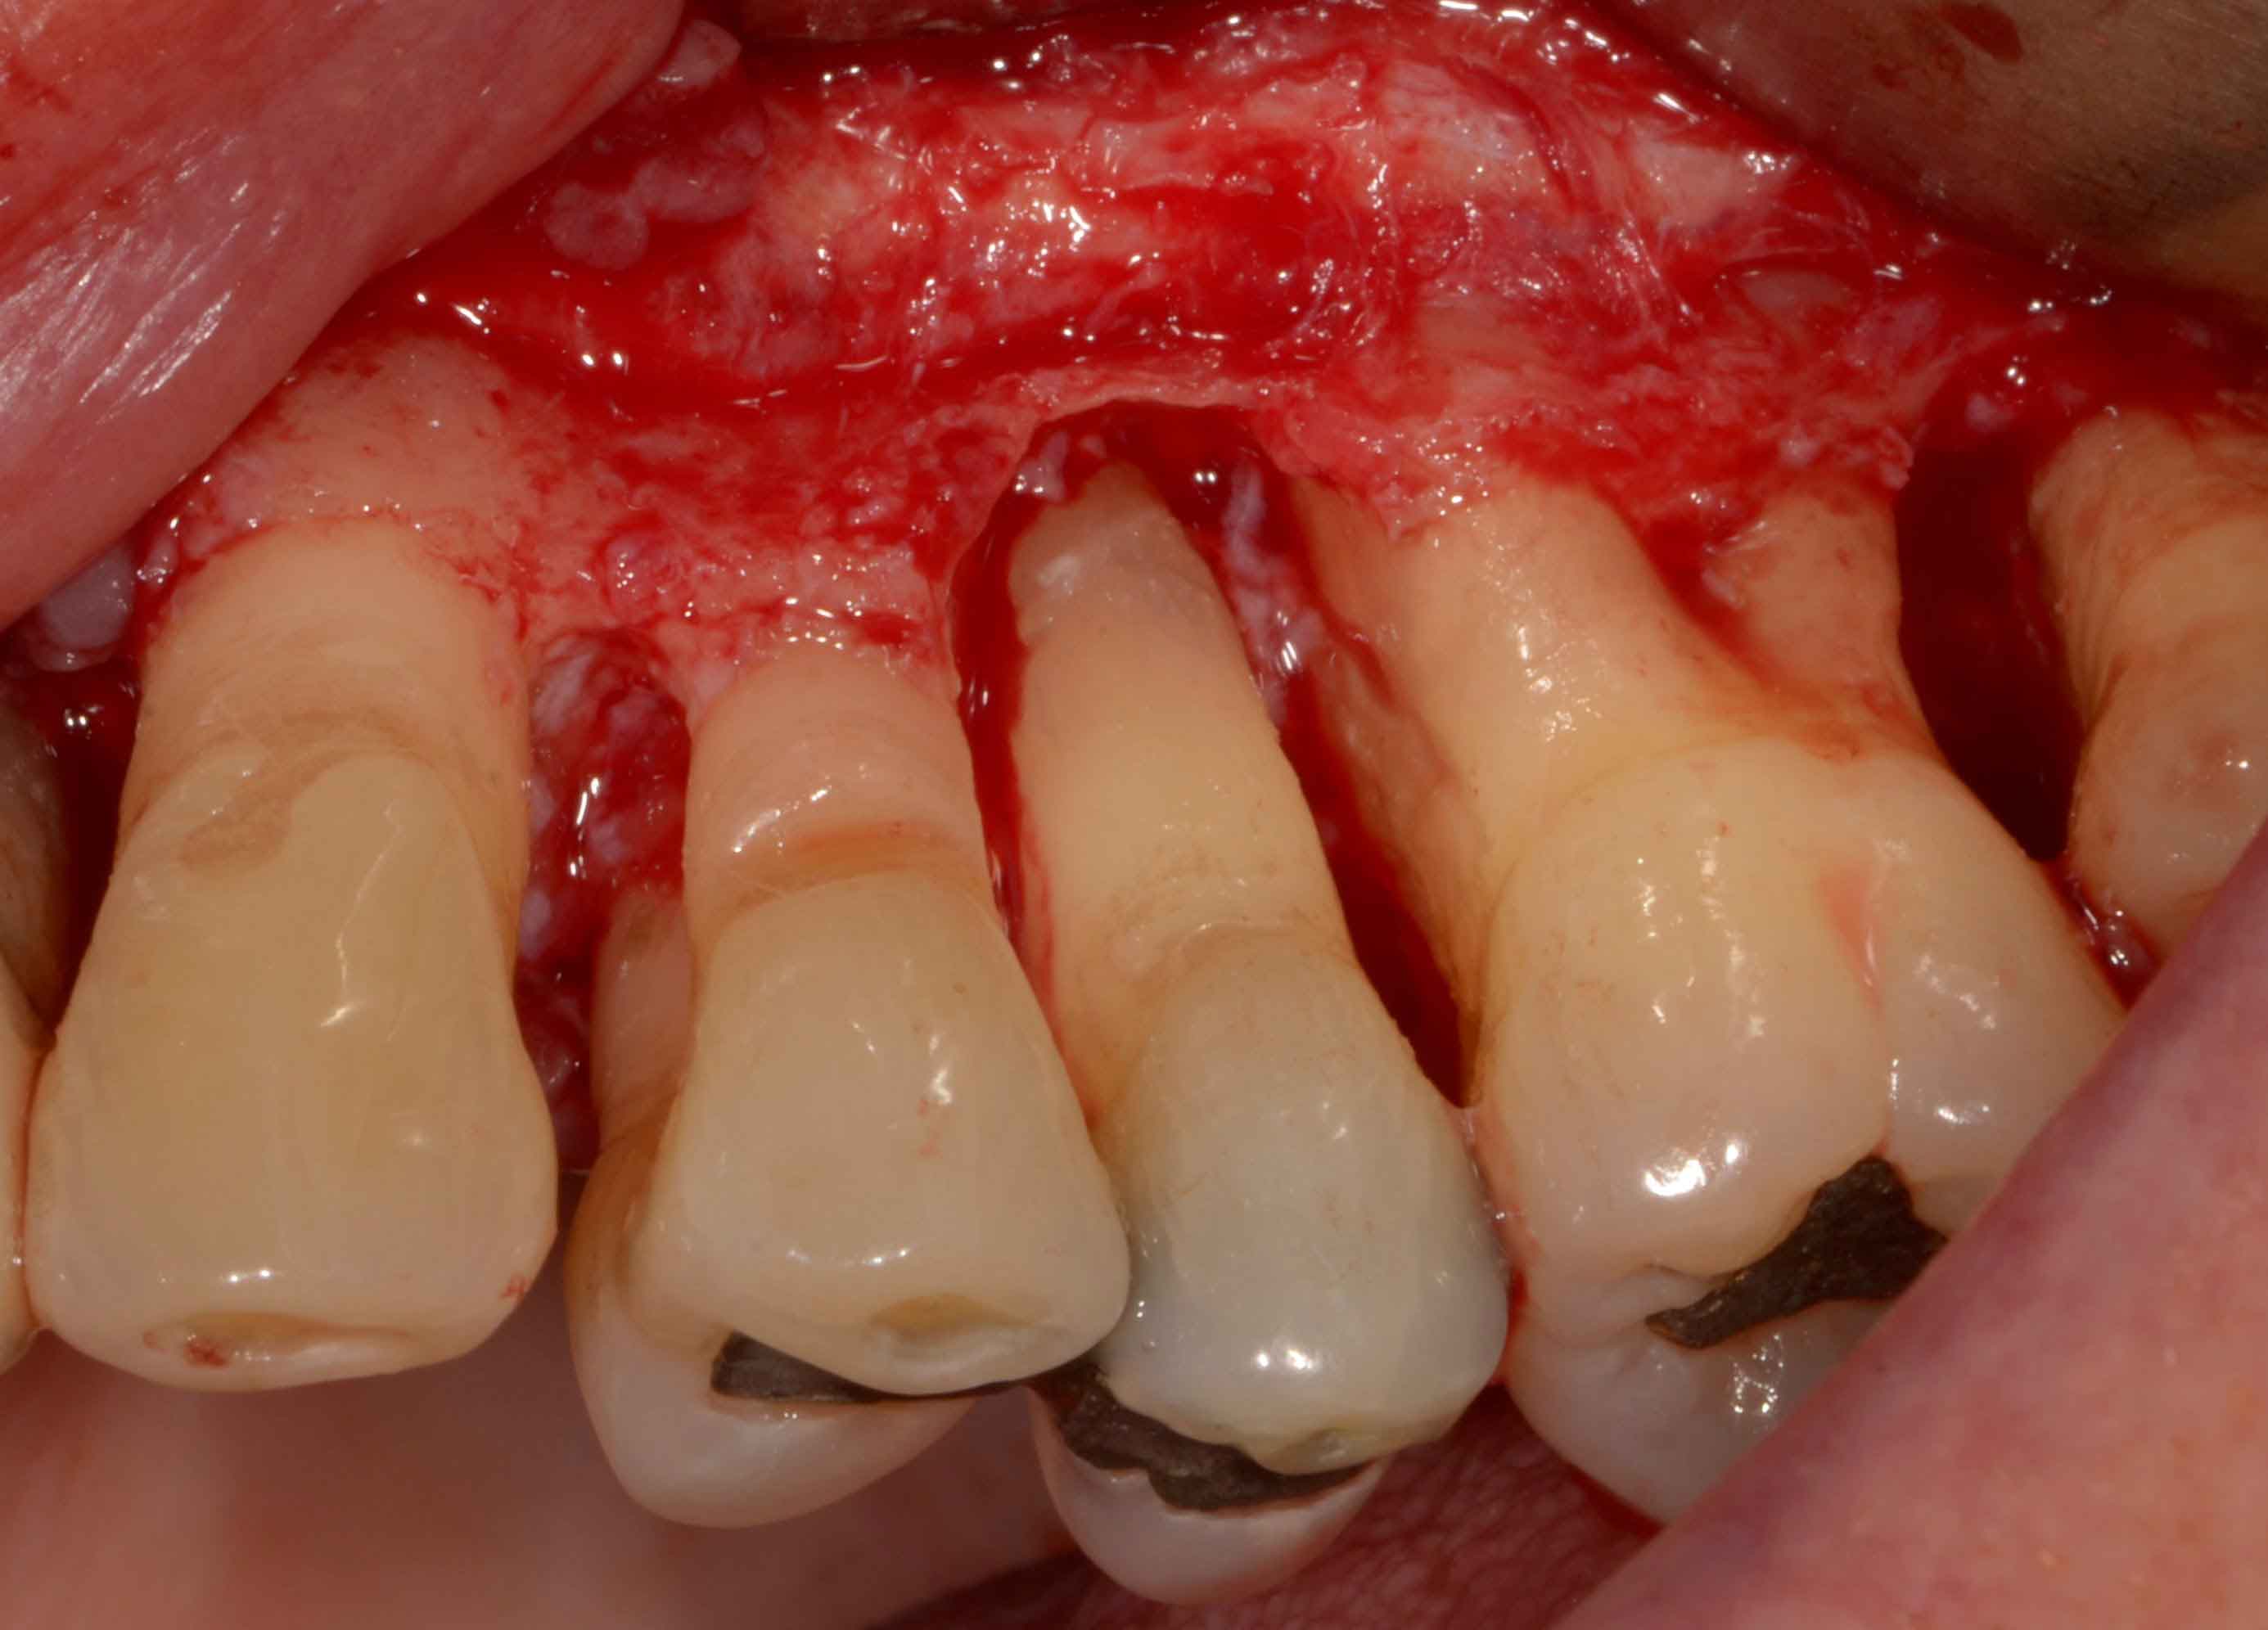

이유가 잇몸과 치아 사이에는 틈이 있는데, 이 틈의 잇몸 선 아래 부분을 박테리아가 공격하여 치주인대와 인접조직을 손상 시키게 되고, 염증이 진행되면 더 많은 조직이 파괴되고 홈이 치주낭으로 발전하게 되며, 치주염이 심할수록 치주낭의 길이가 깊어지게 됩니다.